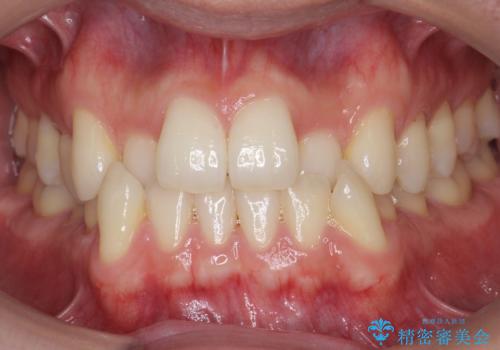

- 前歯のがたつきを気にして来院。

左下の小臼歯が捻転し、反対咬合になっていました。

先にワイヤーで部分矯正を行ってから、インビザラインの部分矯正を行いました。

先に難しい部分をワイヤー矯正することで、インビザラインの部分矯正コースで短期間で予算も抑えて確実に治すことができます。

専門的な話になりますが、下顎の小臼歯は円柱状の形をしており、インビザライン単独では捻転はほぼ治りません。

今回は左下の小臼歯が捻転が強く、そこが反対咬合になっていたため事前に部分矯正を行いました。